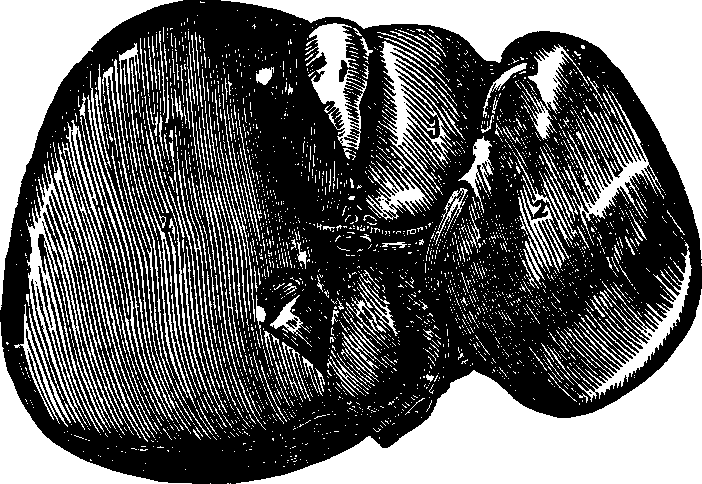

Fig. 33. The inferior surface of the liver. 1. Right lobe. 2.

Left lobe. 3. Gall-bladder.

The Liver, which is the largest gland in the body, weighs [pg 43]about four

pounds in the adult, and is located chiefly on the right side, immediately

below the diaphragm. It is a single organ, of a dark red color, its upper

surface being convex, while the lower is concave. It has two large lobes,